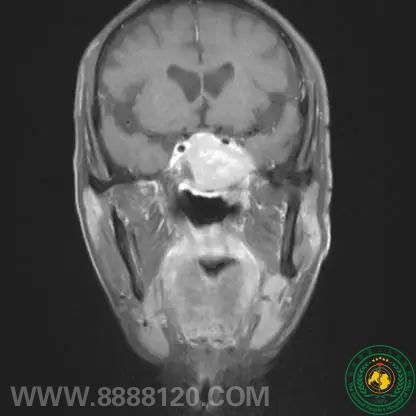

术后图像

术后病检提示为脑膜瘤(WHO-I级)